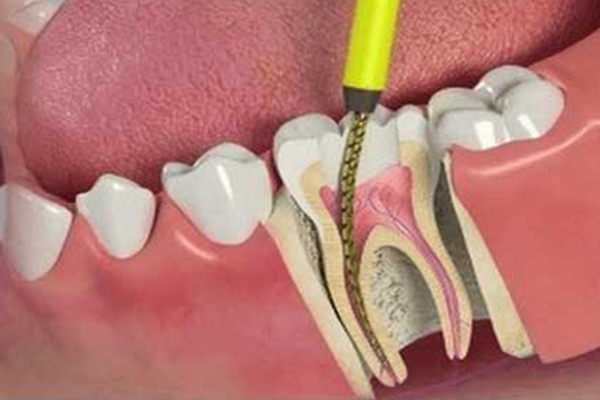

Root canal treatment is needed when the blood or nerve supply of the tooth is infected through decay or injury. The aim of the treatment is to remove all infection from the root canal. The root is then cleaned and filled to prevent any further infection.